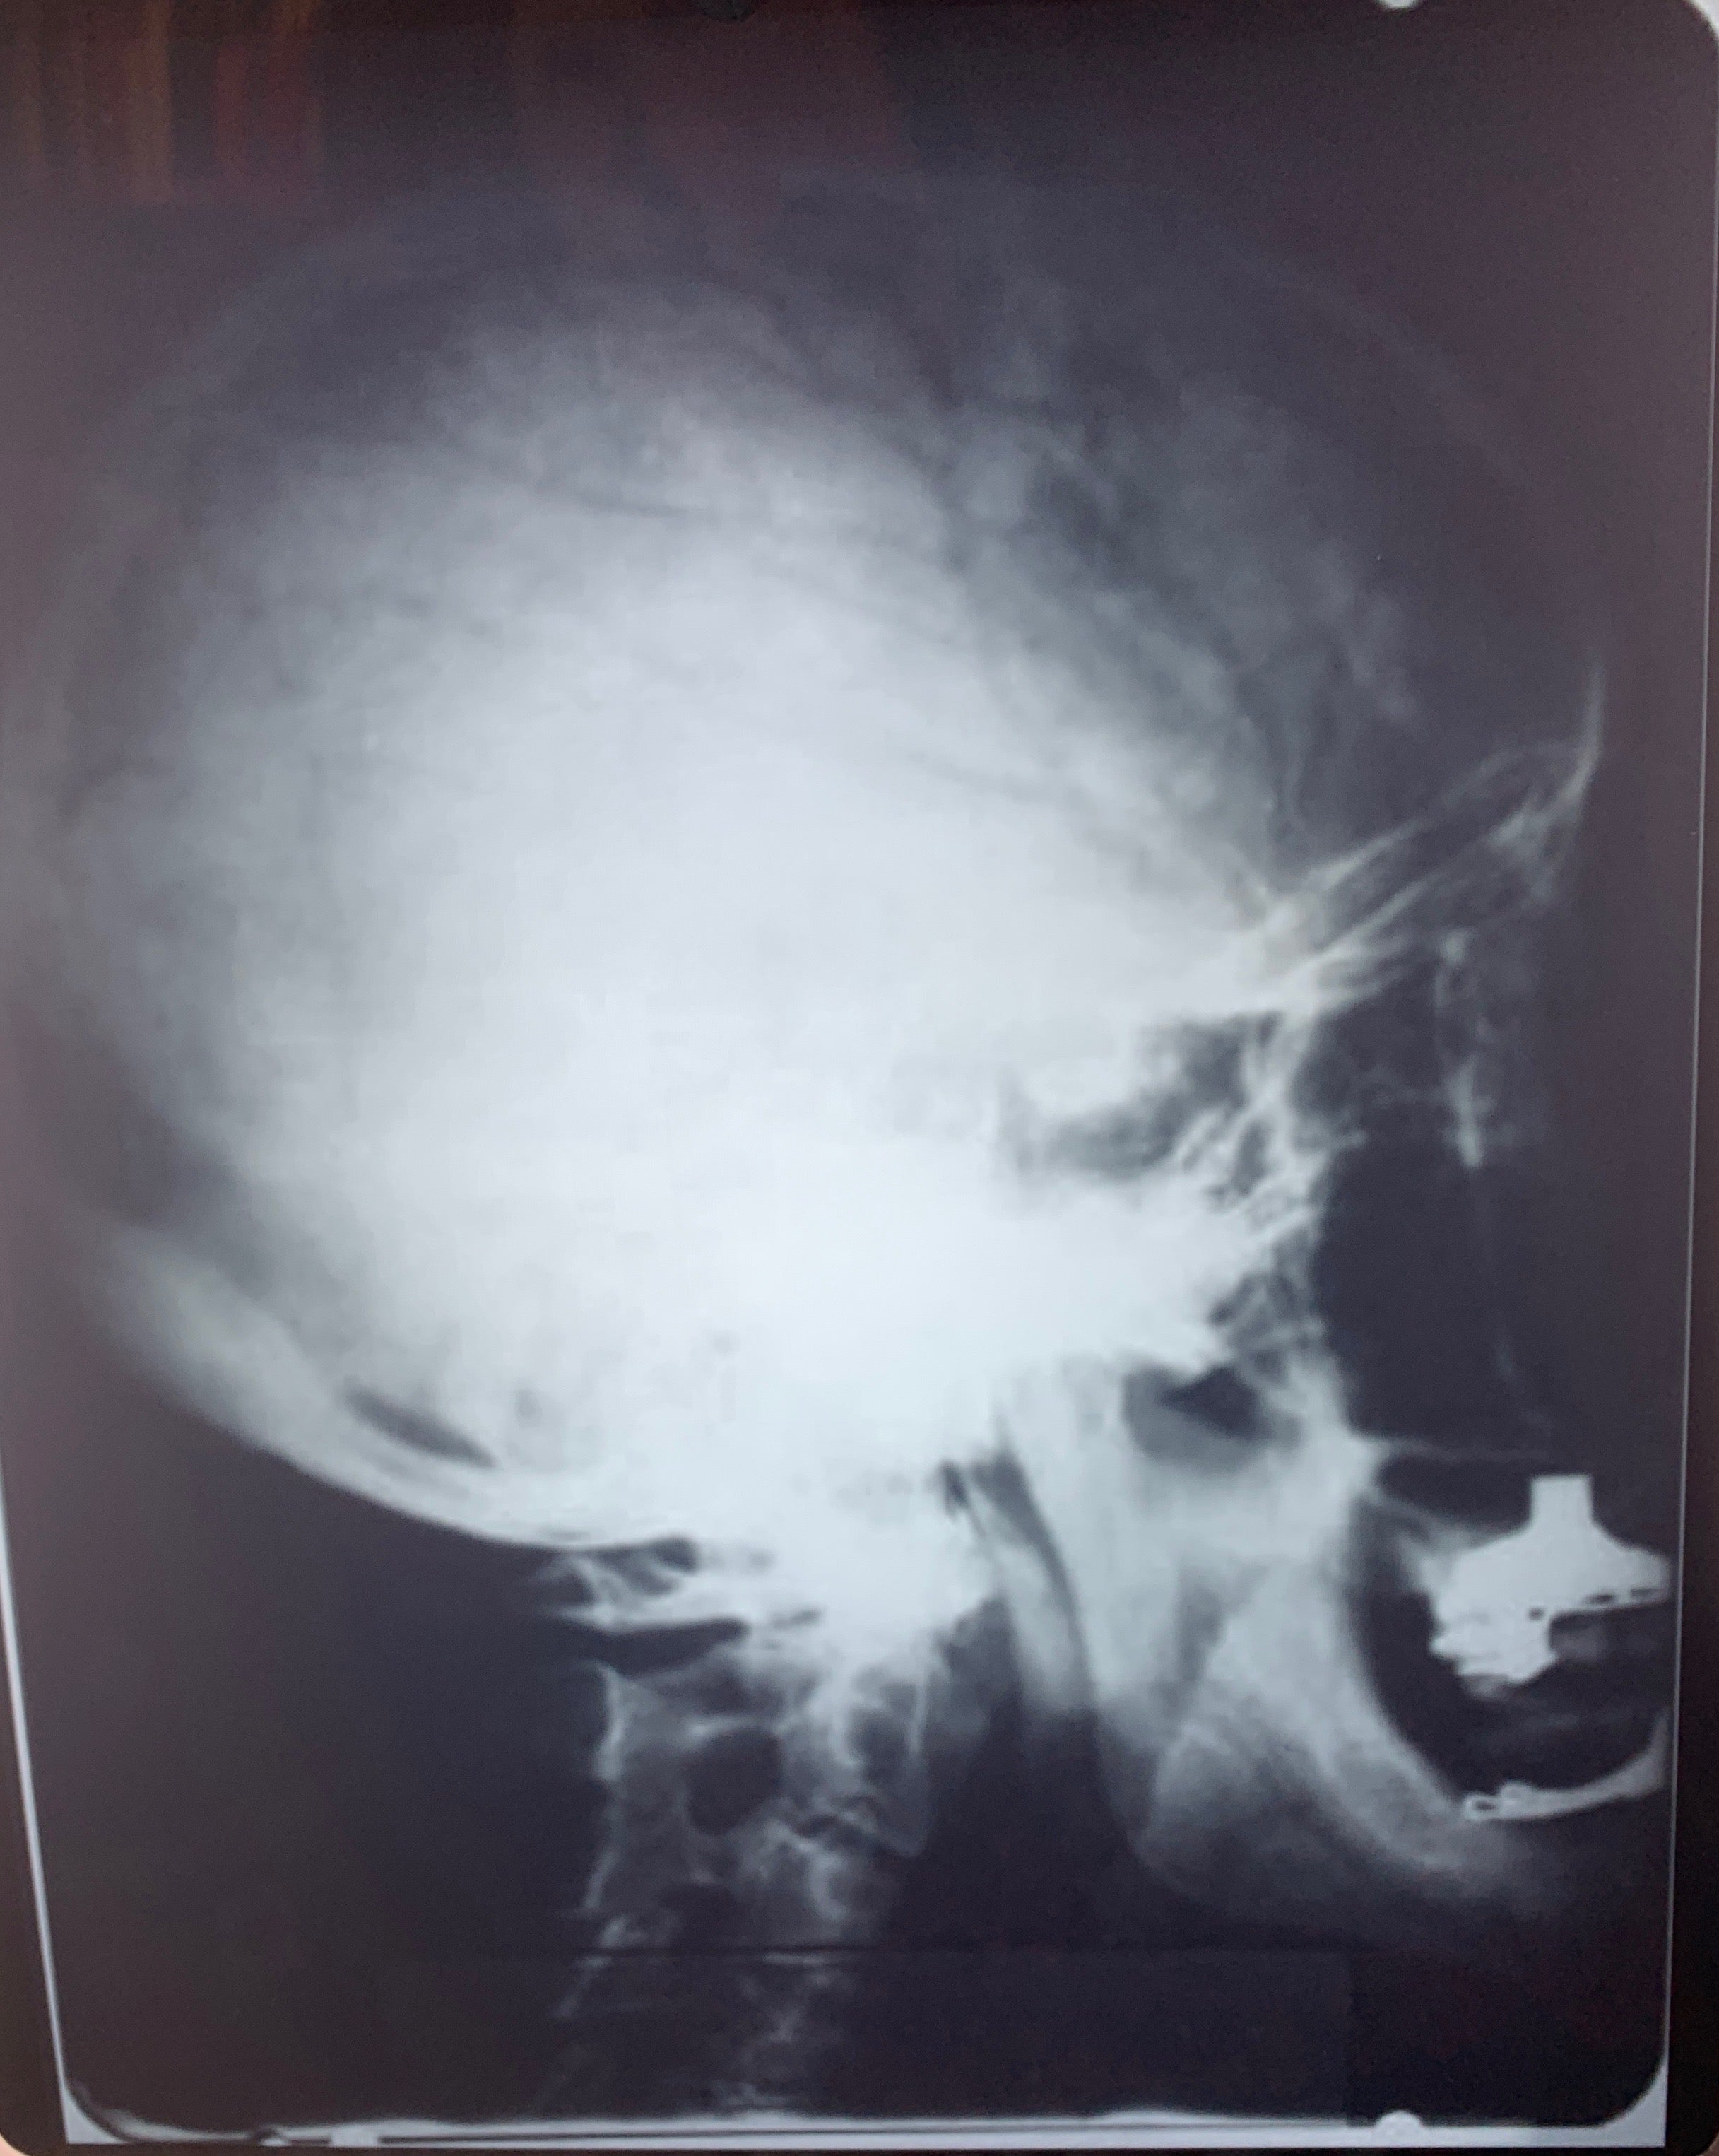

[Einstein, Albert. (1879 - 1955)]. Photograph of Einstein's Brain Waves!. Medical side view X-ray of Albert Einstein's skull, taken in 1945 by Dr. Gustav Bucky. In very fine condition. Printed on standard X-ray photograph stock, 10 x 12 inches (25.2 x 30.2 cm). We have been unable to positively identify when this print was made, but it is not one that either Bucky or Einstein owned and certainly dates from well after the original imaging. Another example of the present X-ray together with a peripheral view (both also later printings), sold on December 2010 at auction for $38,750.00.

Gustav Bucky was a forerunner in radiograph technology and inventor of the Bucky Screen, which allowed for sharper radiograph images. Bucky and Einstein were co-inventors of the Automatic Electric Eye Camera. In 1933, like Einstein, Bucky, who in 1913 had developed a two-plate system that made x-rays a practical medical application, immigrated to the United States where the two met in 1933 while Bucky was treating Einstein’s wife, Elsa. They became close friends and Einstein helped Bucky patent some of his radiological inventions. Additionally, in 1935, they patented a camera that could automatically adjust for exposure using a photoelectric sensor; the camera was never built, however, and with the 1938 production of the automatic Super Six-20, Kodak was credited with creating the first automatic exposure camera. The two remained close friends, and Bucky was at Einstein’s bedside at the time of his death.